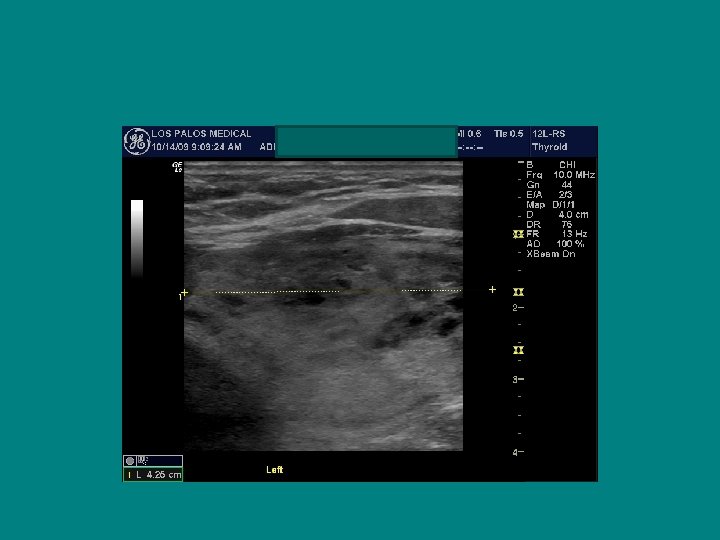

Right Left